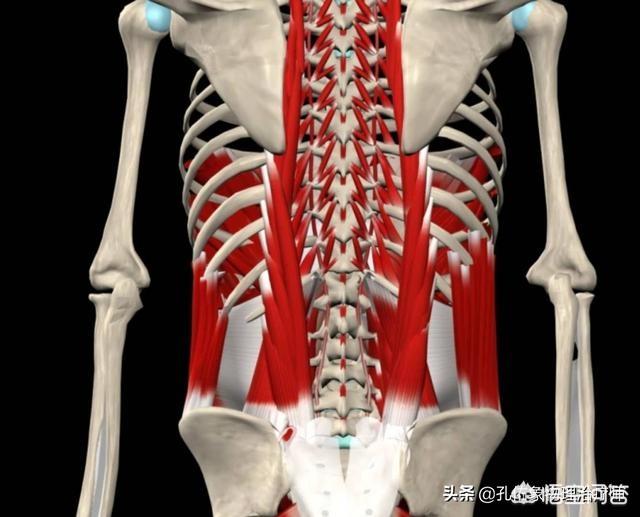

腰椎の歪みは、腰部の筋肉、筋膜、靭帯の軟部組織の慢性的な損傷であり、機能性腰痛症や慢性腰痛症としても知られる腰痛の中で最も一般的な症状です。

腰部筋緊張は、腰部の軟部組織の慢性的な緊張障害の一つであり、この仲間には他にも筋膜緊張や靭帯緊張などがあります。そして、腰部筋緊張は、腰部の筋肉とその付着部である筋膜や骨膜の慢性的な損傷性炎症であり、ほとんどの人にとって腰痛の一般的な原因となっています。

生活の中で、前かがみの姿勢や腰に負担のかかる労働やスポーツに従事することが多く、座りっぱなしで運動不足になりがちな場合。腰部に軽微な損傷が繰り返し蓄積されると、腰部筋付着部、骨膜、靭帯などの組織に病的変化が生じ、神経終末を刺激・圧迫して腰痛症状を生じ、これを腰部筋緊張という。

ぎっくり腰腰背部には、私たちの腰を後方に直立に維持するための要となる最も強力な筋肉である仙骨筋や、横棘を持つ椎骨の横突起にある半棘筋、多裂筋、梨状筋、さらに深部の短筋である横筋間筋、棘間筋など多くの筋肉があり、腰がどのような姿勢であっても、腰背部の筋肉は収縮状態にあり、重力に抵抗しなければならないため、腰背部の筋肉に疲労が生じます。どのような姿勢であっても、腰の筋肉は収縮状態にあり、重力に抵抗しなければならないため、腰椎の筋肉が疲労してしまうのです。

腰椎の筋緊張は、主に腰椎の筋肉の過度の疲労に起因する慢性的な累積損傷であり、そのような長期的な前かがみの仕事、習慣的な悪い姿勢、固定された位置に長い時間、筋肉、筋膜や靭帯が引っ張り続ける結果、筋膜の圧力が増加するように、血液供給が良好ではない、労作の収縮の筋線維は、エネルギーの消費量は、痛みによって引き起こされる乳酸の多数をもたらし、サプリメントにタイムリーにアクセスすることはできませんし、変化の繰り返しの蓄積。性、炎症性刺激を引き起こす。